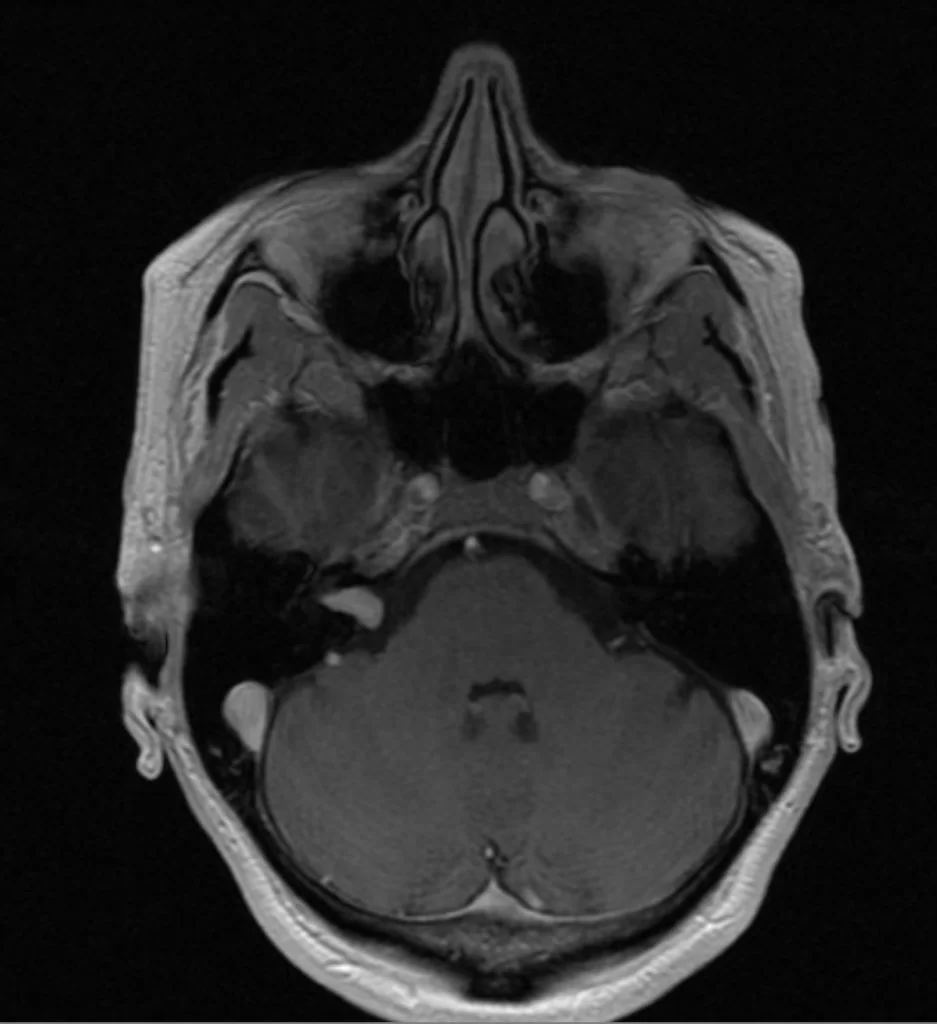

Ασθενής άνδρας, 31 ετών με επεισόδια κεφαλαλγίας. H Μαγνητική Τομογραφία εγκεφάλου ανέδειξε εκτεταμένη χωροκατακτητική εξεργασία δεξιά κροταφικά με πίεση επί του σύστοιχου κροταφικού κέρατος και

Περισσότερα